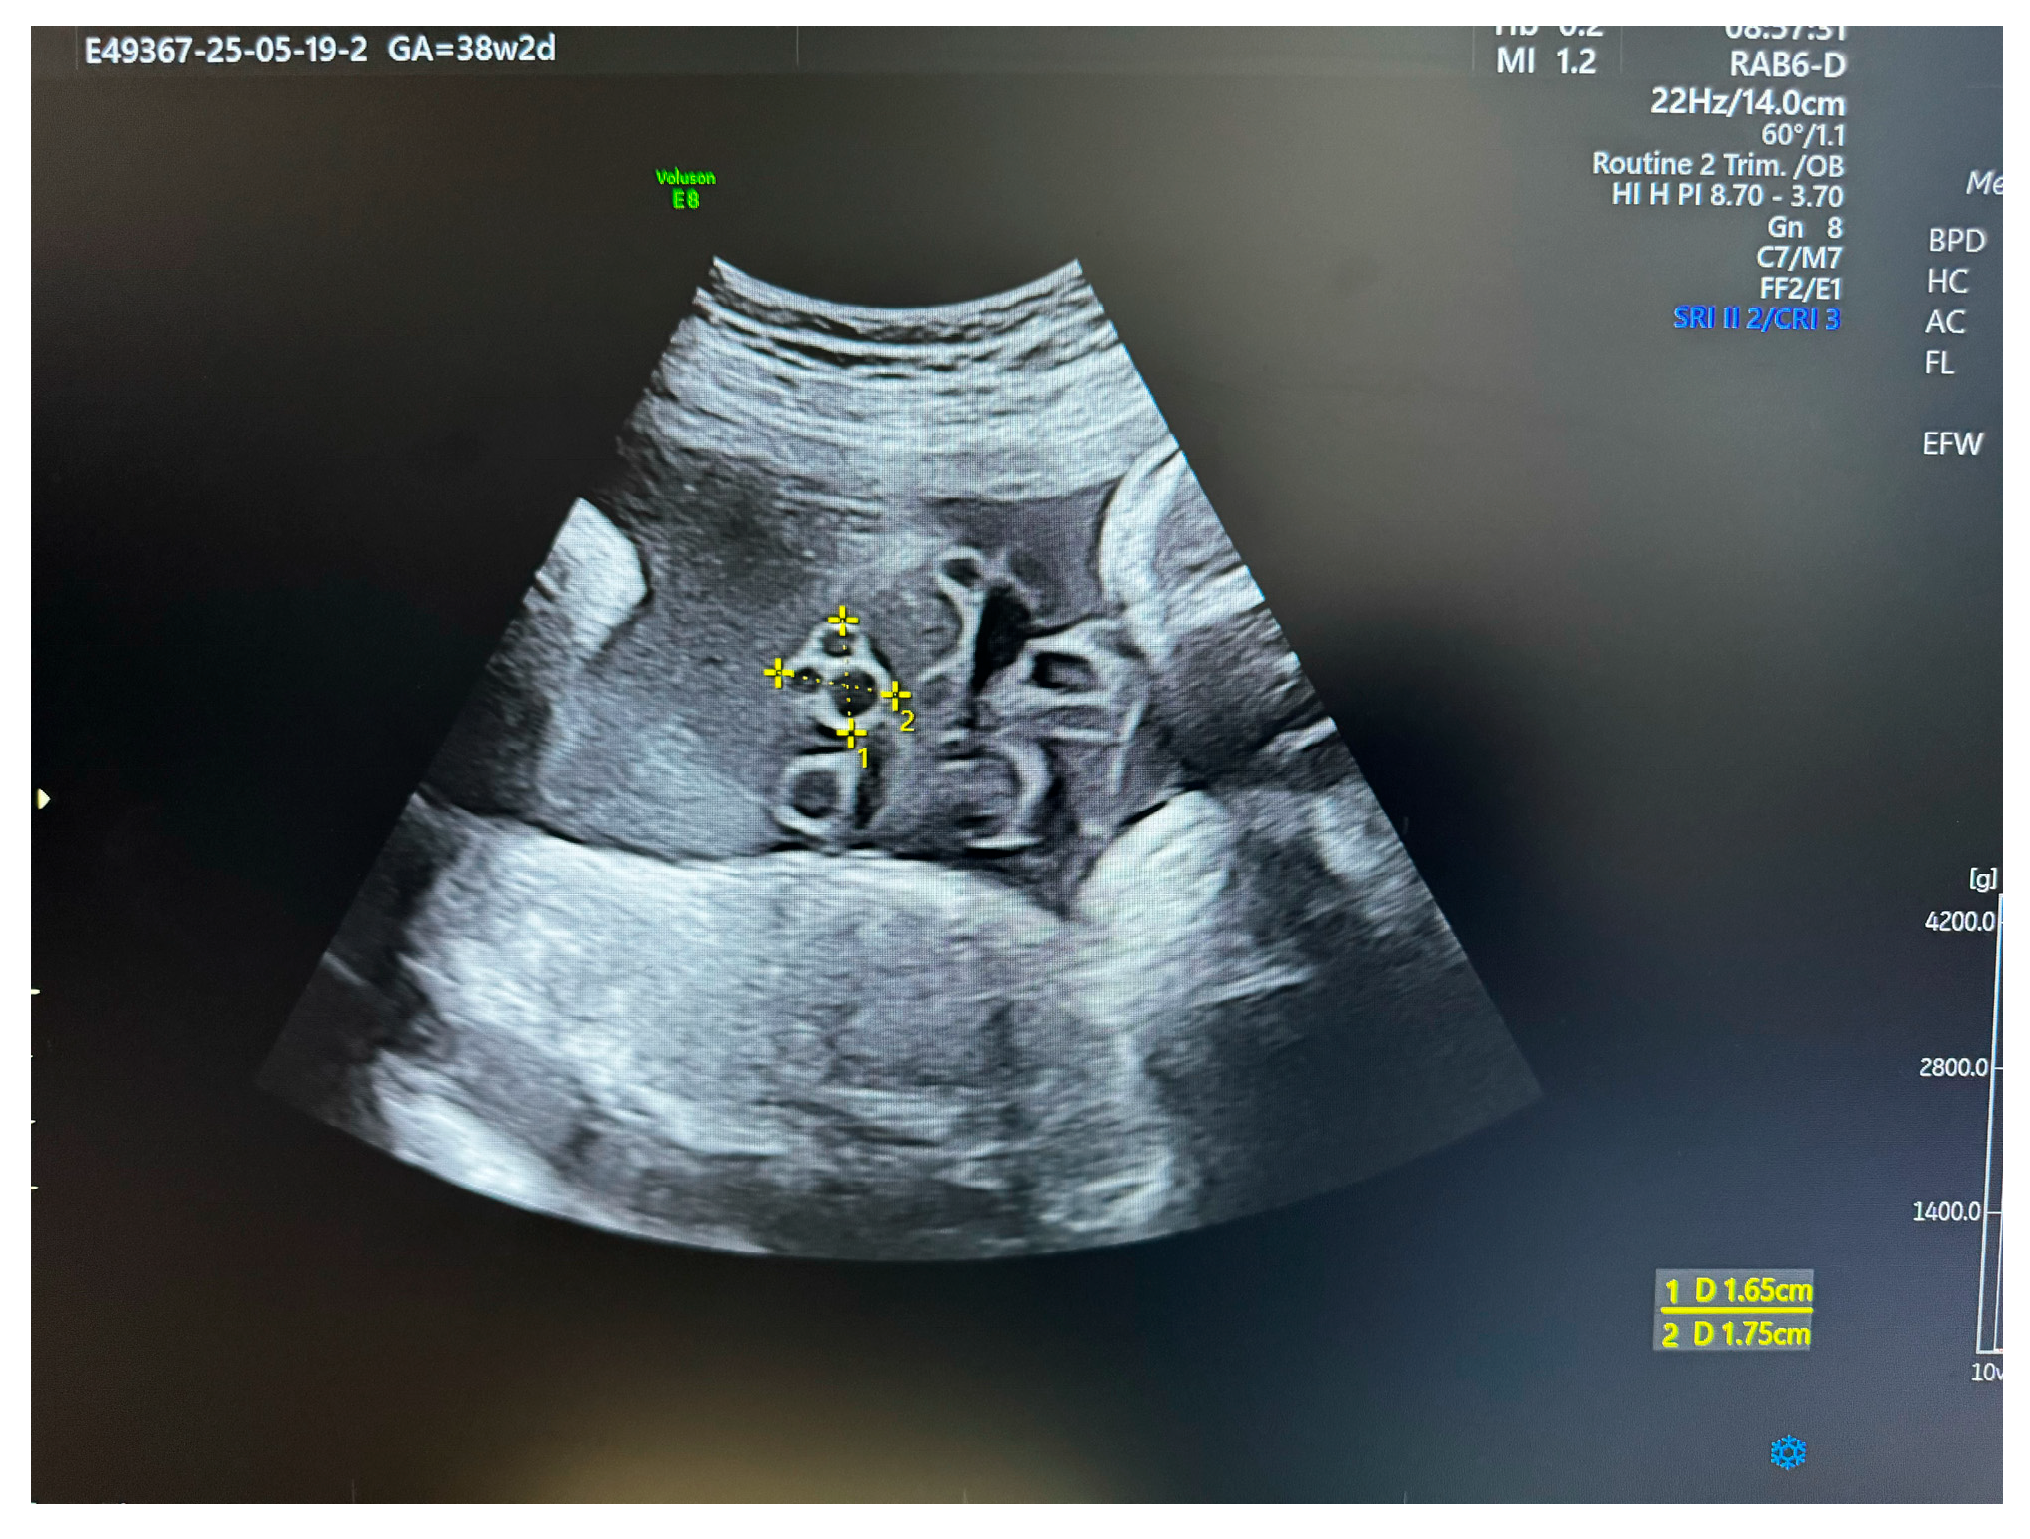

Sonographic Assessment

Diagnosing Cysts and Edema